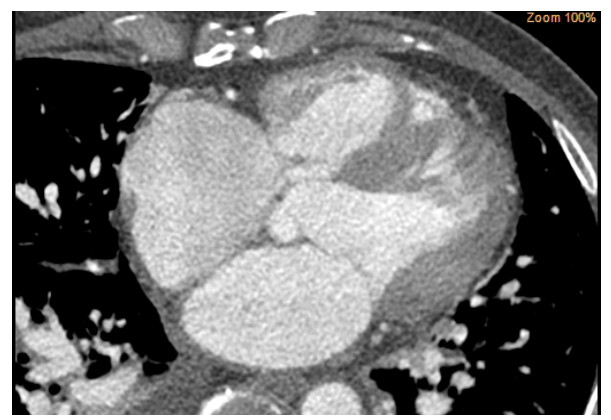

术前心脏计算机断层扫描血管造影(computed tomographyangiography, CTA)检查未能明确诊断右乏氏窦瘤破裂(图 4),这给临床医生带来一定困惑。经急诊超声心动图检查及临床医生全面评估后行右乏氏窦瘤破裂修复术和主动脉瓣成形术。取适当大小的牛心包补片,间断褥式缝合修补破口及室间隔夹层,并行主动脉瓣成形术。术中经食道超声心动图显示窦瘤破裂修补完好,分流消失,主动脉瓣瓣叶开闭良好,反流消失。术后1个月复查,二维超声心动图显示主动脉短轴切面:右乏氏窦瘤破裂修补处回声增强,连续性好;CDFI:该处分流消失。主动脉瓣瓣叶开闭正常。胸骨旁四腔心切面显示如上(图 5),室间隔回声稍不均质,室间隔夹层动脉瘤完全塌陷,未见夹层动脉瘤显示。

| 图 4 CTA未能明确诊断右乏氏窦瘤破裂 |